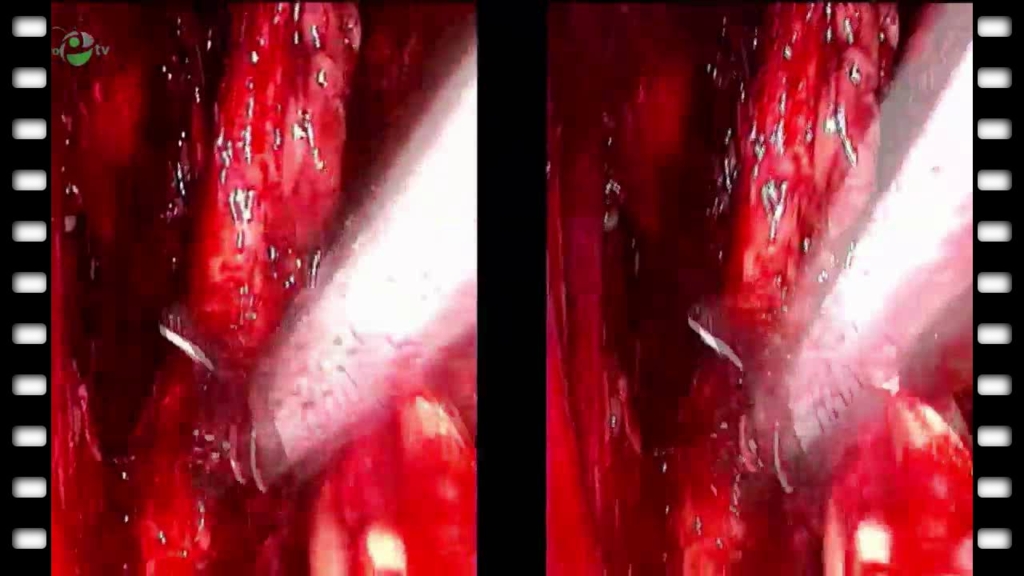

Видеоэндоскопическая экстрафасциальная радикальная простатэктомия. Тазовая лимфоаденэктомия (3D)